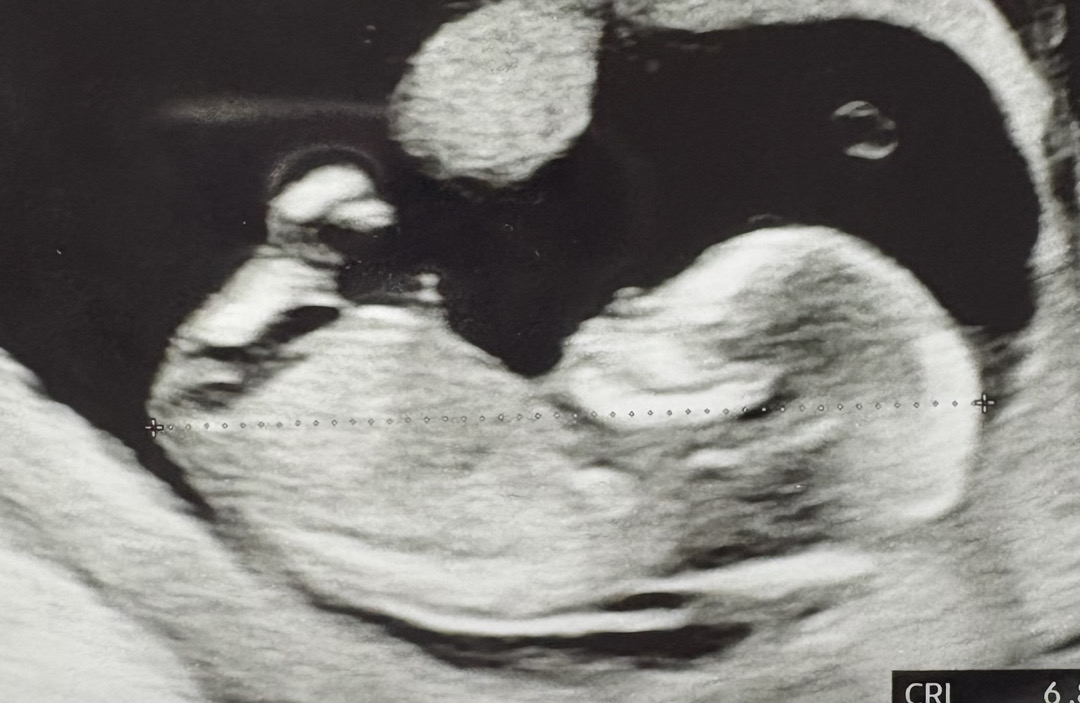

13주4일찬데 성별 뭘로 보이세요?!

13주4일차에요 ㅎㅎ 의사선생님은 80프로 딸같다고 하시는데 아들같기도하고 ....

다리 때문에 안보여용